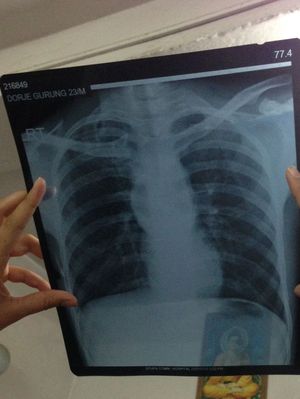

Chest X-ray

Can anyone guess the diagnosis?

Not quite! Look at the white blotches - those are a good clue.

I do not know,maybe sarcoidosis or old tuberculosis?!

But the aorta a bit enlarged, is it aneurysm? And the heart looks a too tubular or small?

Calcified hilar lymphadenopathy is characteristic.

Élargissement du médiastin : Aortique aneurysm? Thymome? Goitrre plongeant? .......+ surelévation de la pointe du avec détérioration: Fallope tétralogy?........ we can also see calcifications: healed infection,maby tuberculosis?

Right sided pneumothorax with aortic aneurysm